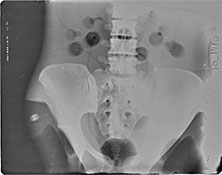

BREAK-APART PIXY Pelvis X-Ray BREAK-APART PIXY Knees X-Ray 1 BREAK-APART PIXY Knees X-Ray 2